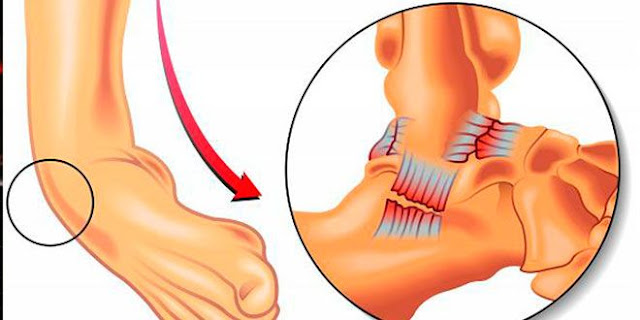

|

| Ejercicios fisioterapéuticos de mano |

Para evitarlo, se recomienda abrir y cerrar las manos varias veces al día o flexionando y extendiendo los tobillos. De esta forma se ve favorecido el retorno venoso, evitando trombosis o cierto tipo de edemas.